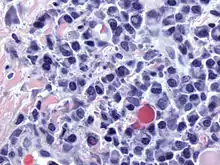

![]() Micrograph of malignant plasma cells (plasmacytoma), many displaying characteristic "clockface nuclei", also seen in normal plasma cells. H&E stain. | |

Plasmacytoma, multiple myeloma, Waldenström macroglobulinemia, heavy chain disease, and plasma cell leukemia are malignant neoplasms ("cancer") of the plasma cells.[33] Multiple myeloma is frequently identified because malignant plasma cells continue producing an antibody, which can be detected as a paraprotein.